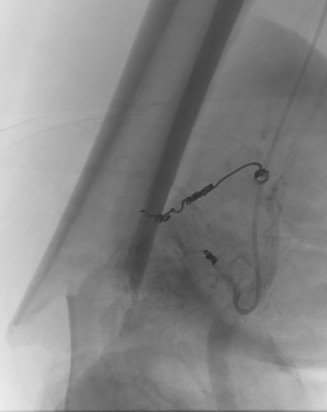

Pre-operative Arterial Embolization

Indications

- renal cell carcinoma

- thyroid carcinoma

Results

- embolisation of RCC metastasis in 107 patients

- success in 96%

- all patients had variable ischemic pain for 2 - 4 day

- 41 cases with embolization prior to surgery compared to 41 cases without

- embolization reduced blood loss, transfusion, and surgical times